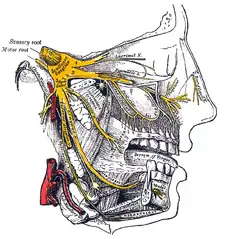

E. Nerves of the nose

The sensations registered by the human nose derive from the first two branches of cranial nerve V, the trigeminal nerve. The nerve listings indicate the respective innervation (sensory distribution) of the trigeminal nerve branches within the nose, the face, and the upper jaw (maxilla).

- The indicated nerve serves the named anatomic facial and nasal regions

Ophthalmic division innervation

- Lacrimal nerve – conveys sensation to the skin areas of the lateral orbital (eye socket) region, except for the lacrimal gland.

- Frontal nerve – conveys sensation to the skin areas of the forehead and the scalp.

- Supraorbital nerve – conveys sensation to the skin areas of the eyelids, the forehead, and the scalp.

- Supratrochlear nerve – conveys sensation to the medial region of the eyelid skin area, and the medial region of the forehead skin.

- Nasociliary nerve – conveys sensation to the skin area of the nose, and the mucous membrane of the anterior (front) nasal cavity.

- Anterior ethmoid nerve – conveys sensation in the anterior (front) half of the nasal cavity: (a) the internal areas of the ethmoid sinus and the frontal sinus; and (b) the external areas, from the nasal tip to the rhinion: the anterior tip of the terminal end of the nasal-bone suture.

- Posterior ethmoid nerve – serves the superior (upper) half of the nasal cavity, the sphenoids, and the ethmoids.

- Infratrochlear nerve – conveys sensation to the medial region of the eyelids, the palpebral conjunctiva, the nasion (nasolabial junction), and the bony dorsum.

The maxillary division innervation

- Maxillary nerve – conveys sensation to the upper jaw and the face.

- Infraorbital nerve – conveys sensation to the area from below the eye socket to the external nares (nostrils).

- Zygomatic nerve – through the zygomatic bone and the zygomatic arch, conveys sensation to the cheekbone areas.

- Superior posterior dental nerve – sensation in the teeth and the gums.

- Superior anterior dental nerve – mediates the sneeze reflex.

- Sphenopalatine nerve – divides into the lateral branch and the septal branch, and conveys sensation from the rear and the central regions of the nasal cavity.

The supply of parasympathetic nerves to the face and the upper jaw (maxilla) derives from the greater superficial petrosal (GSP) branch of cranial nerve VII, the facial nerve. The GSP nerve joins the deep petrosal nerve (of the sympathetic nervous system), derived from the carotid plexus, to form the vidian nerve (in the vidian canal) that traverses the pterygopalatine ganglion (an autonomic ganglion of the maxillary nerve), wherein only the parasympathetic nerves form synapses, which serve the lacrimal gland and the glands of the nose and of the palate, via the (upper jaw) maxillary division of cranial nerve V, the trigeminal nerve.